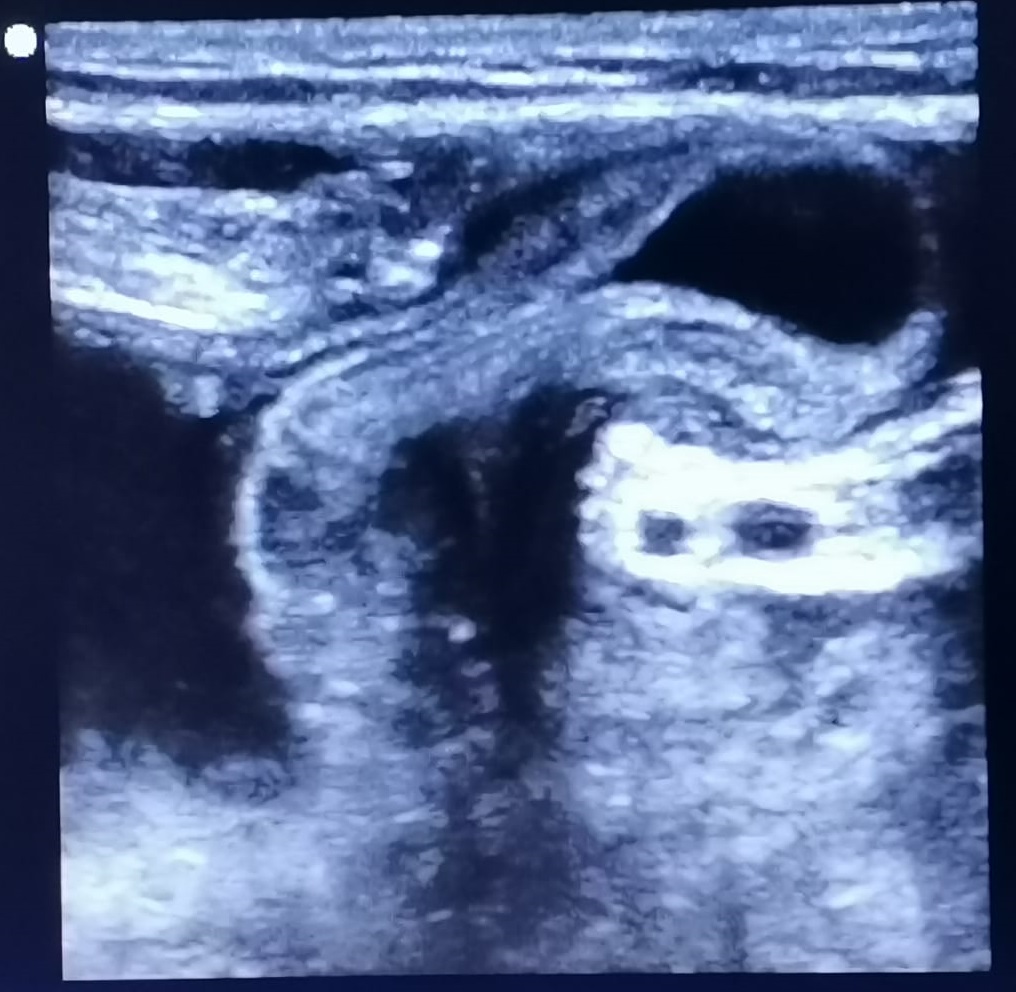

Ecografía a pie de cama: protusión de contenido hipoecogénico a través de agujero herniario, que aumenta su diámetro con maniobra de Valsalva y que no se reduce por completo; compatible con hernia inguinocrural no reductible.